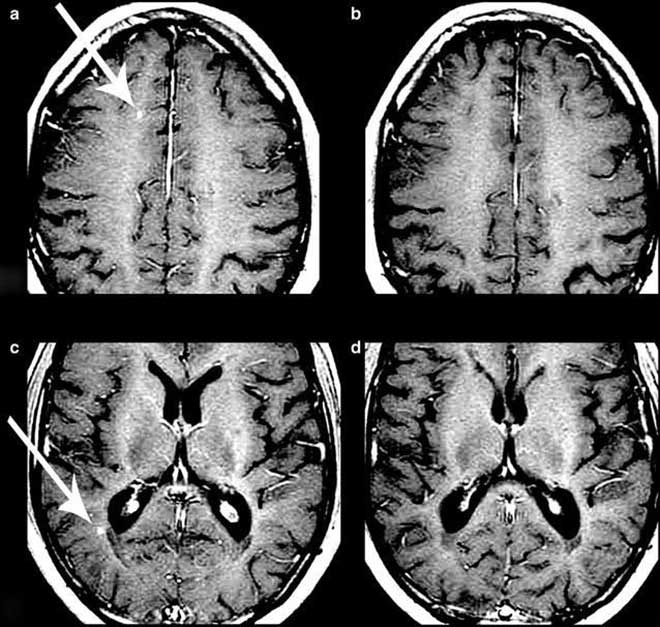

两位患者治疗前后磁共振成像的变化(四川省干细胞库提供)

治疗后一年的MRI扫描显示,18名评估患者中有15名无活动性病变,其中1名患者的脑部病变几乎完全消除,研究人员认为,“这是一个特别令人鼓舞的发现”。在这一年中,患者的残疾水平也逐渐获得改善,在没有外力帮助的情况下,步行和工作能力均有所提高。